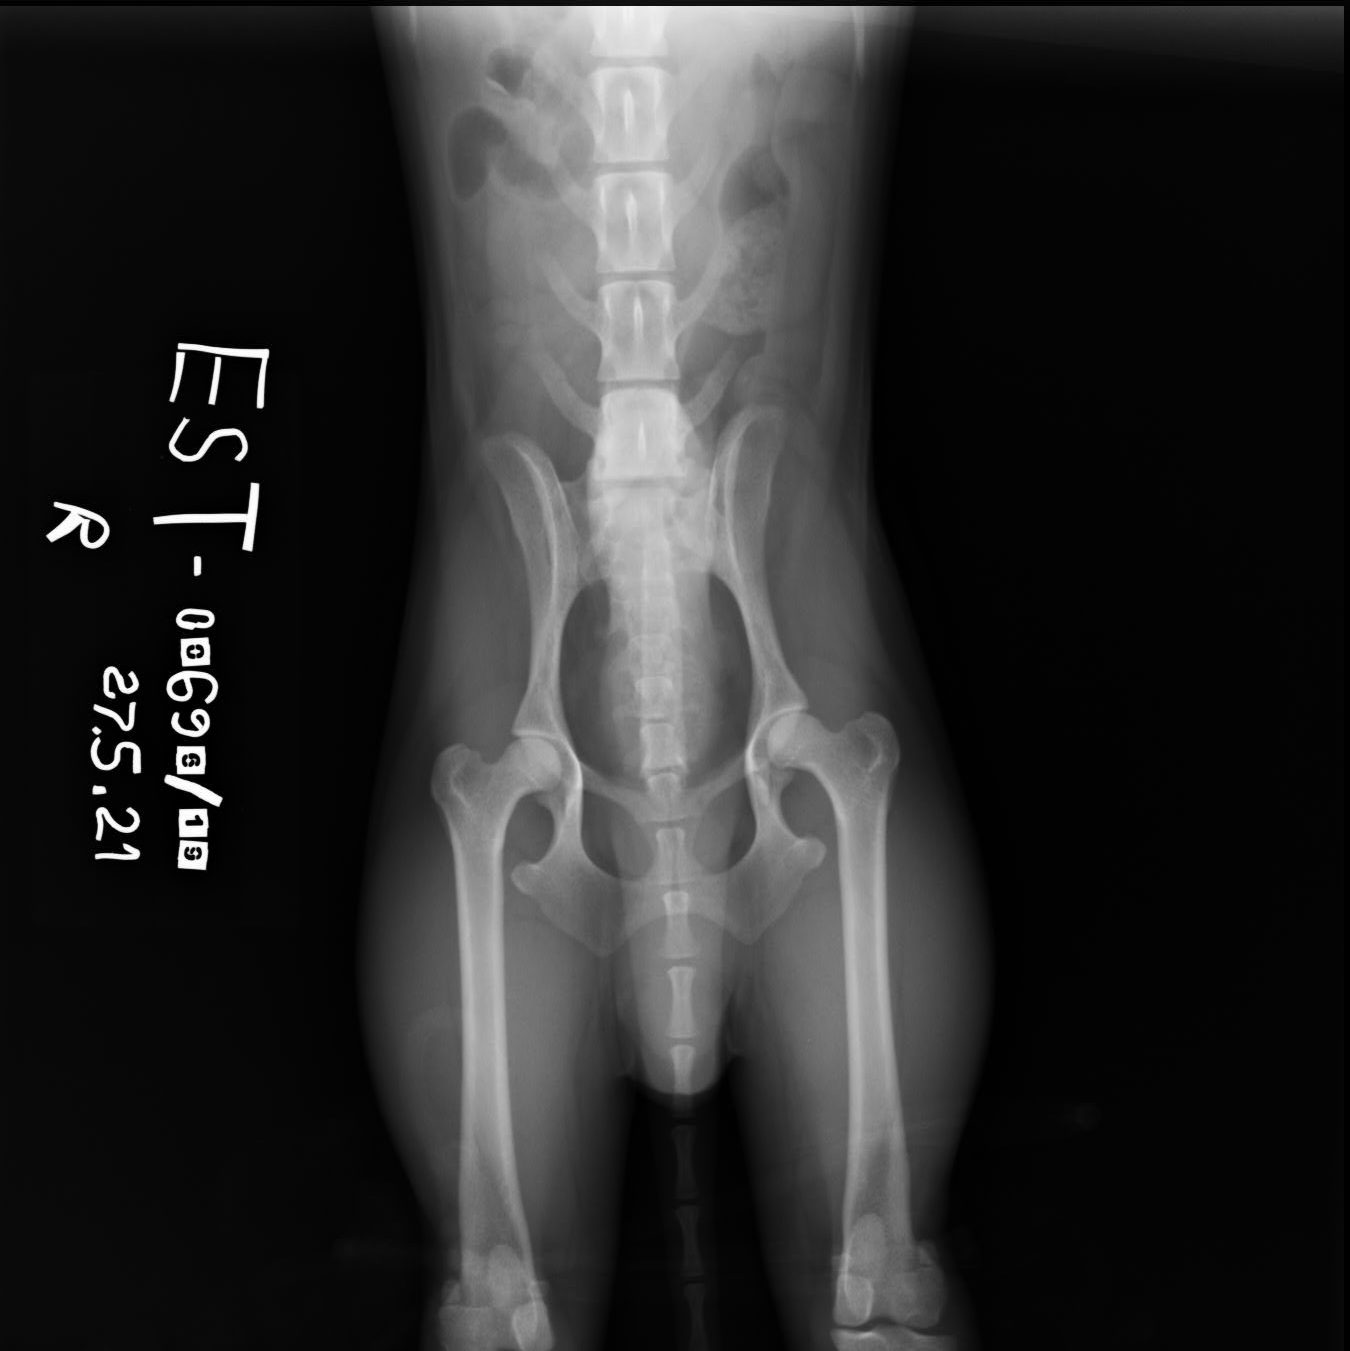

Välimuotoinen lanne-ristinikama (lumbosacral transitional vertebra, LTV)

LTV on yleinen synnynnäinen ja perinnöllinen nikamaepämuodostuma jonka periytymismekanismia ei tunneta.

LTV:llä tarkoitetaan nikamaa, jossa on sekä lanne- että ristinikaman piirteitä. Välimuotoinen nikama voi olla viimeinen lannenikama (L7), jolloin puhutaan sakralisaatiosta tai ensimmäinen ristiluun nikama (S1), jolloin puhutaan lumbalisaatiosta. Muutos voi olla symmetrinen eli samanlainen oikealla ja vasemmalla puolella tai epäsymmetrinen, jolloin selällään otetussa röntgenkuvassa nähdään puoliero.

Joillain koirilla lannenikamien lukumäärä on poikkeava, normaalin 7 nikaman sijaan näillä koirilla on 8 (L8) tai 6 (L6) lannenikamaa.

LTV:stä voi saada lausunnon 12 kuukautta täyttänyt koira.